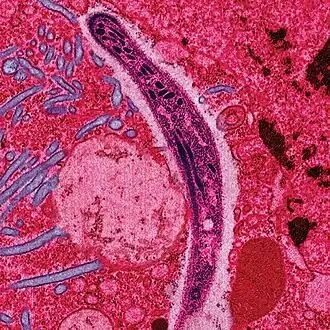

Раскрашенная электронная микрофотография демонстрирует миграцию возбудителя малярии сквозь эпителий кишки. | |